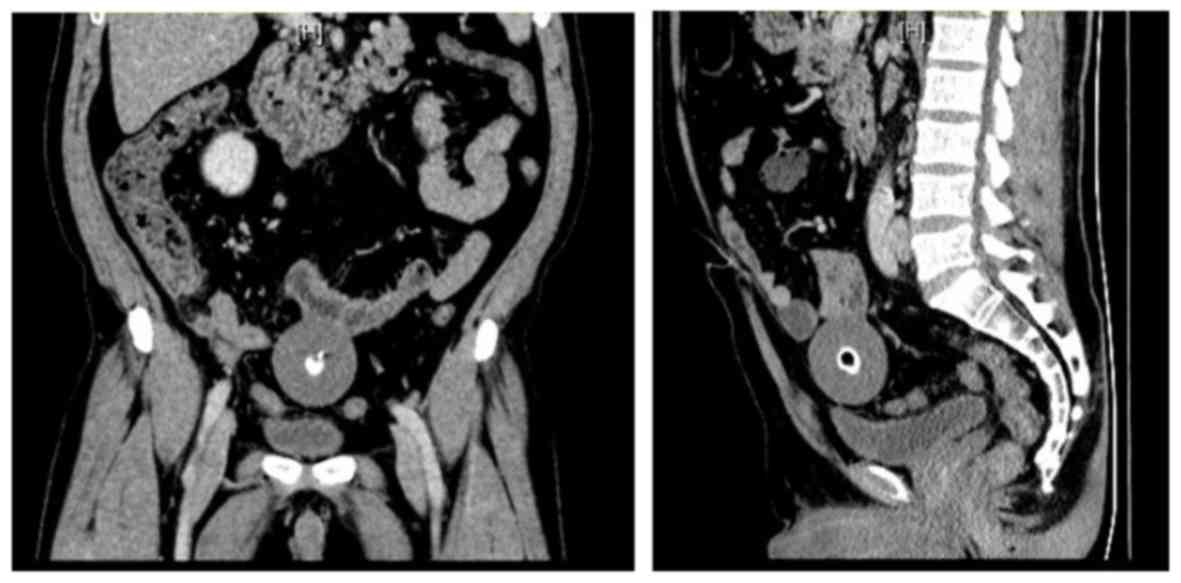

The laboratory tests revealed high levels of γ-glutamyl-transpeptidase (80 U/l; normal range, 0-50 U/l), direct bilirubin and alanine aminotransferase, and increased levels of carcinoembryonic antigen (CEA); infectious markers included positive hepatitis B virus (HBV) markers, namely HB surface antigen, anti-HBe antibody and HB core antibody. An abdominal computed tomography (CT) scan revealed a 5.5x5.0-cm midline mass with central high density (Fig. 1). In addition, the CT examination revealed a fatty liver. Abdominal open surgery was performed to remove the mass, and the postoperative pathological examination revealed that it was composed of hyperplastic fibrillar collagen with partial microcalcifications.

Figure 1.

Anteroposterior (left) and lateral (right) computed tomography images of the patient.

Clinically, PLBs must be differentiated from other tumors, such as mesenteric tumors, leiomyoma and teratoma. Abdominal CT examination may be helpful, as it demonstrates the characteristic features of PLBs, which are well-defined oval or round soft tissue masses with central calcification, usually located in the abdomen, with a distinct fat plane around the mass separating it from adjacent organs (10). Since PLBs are freely mobile, additional scanning in the prone position or a follow-up CT examination can demonstrate the change in location. Moreover, on magnetic resonance imaging (MRI) examination, PLB appears as a well-defined, low-intensity mass on both T1- and T2-weighted images (11). The MRI signal is similar to that of muscle, and a central high-intensity area may be seen on T1-weighted images. PLBs do not exhibit any enhancement, which is useful in differential diagnosis, as leiomyoma and teratoma exhibit contrast enhancement. Performing CT and MRI is crucial for identifying the characteristic features of PLB and establishing an accurate diagnosis.